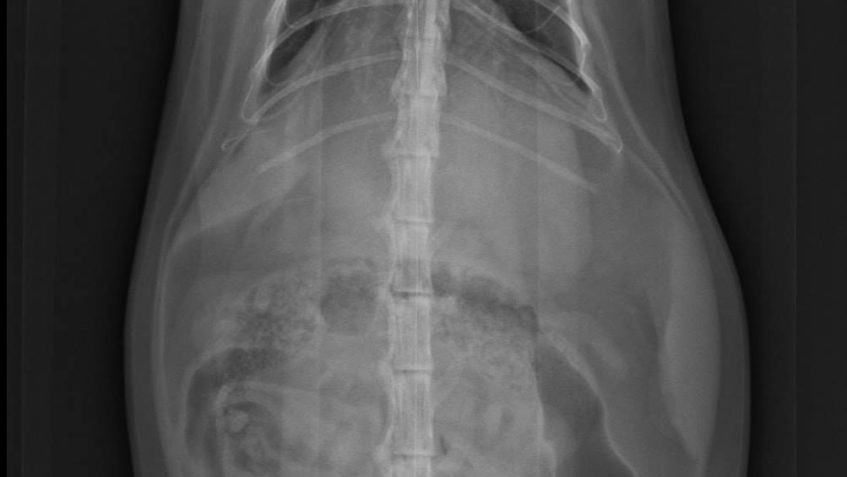

Po sérii vyšetření a RTG byla Donikovi nasazena chemoterapie! 😯

Drobné útvary nádoroveho bujení po celých plicích potvrdila i biopsie.